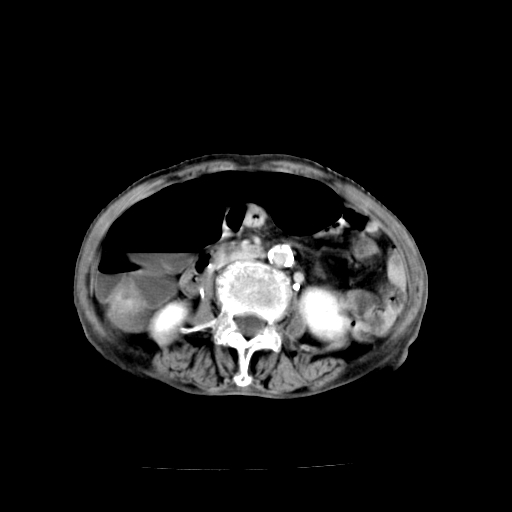

标题: CT19149:女,68岁,腹胀、恶心两周。 [打印本页]

女,68岁,腹胀、恶心两周,先做ct平扫,当时家属不同意强化,6天后家属要求增强扫描。

1、胃窦癌; 2、局灶性脂肪肝。

1、胃窦癌?建议行胃镜!; 2、局灶性脂肪肝。

1)胃窦壁厚,考虑胃窦癌?建议行胃镜检查。 2)局灶性脂肪肝。

支持考虑1、胃窦癌?建议行胃镜!; 2、局灶性脂肪肝。  3、双侧胸腔积液,胸膜增厚